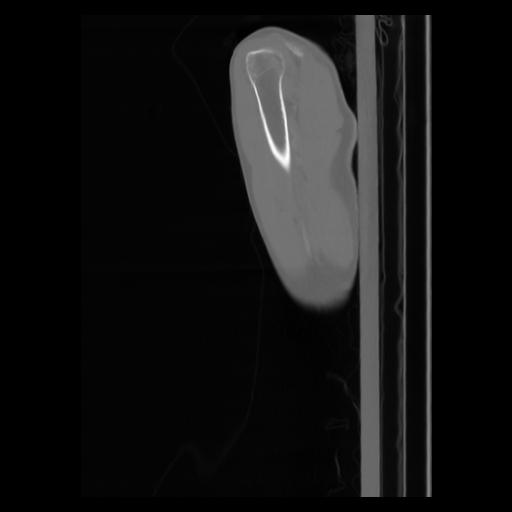

30 CUERPO,CE,Sagittal,3.000,CUERPO,Sagittal,